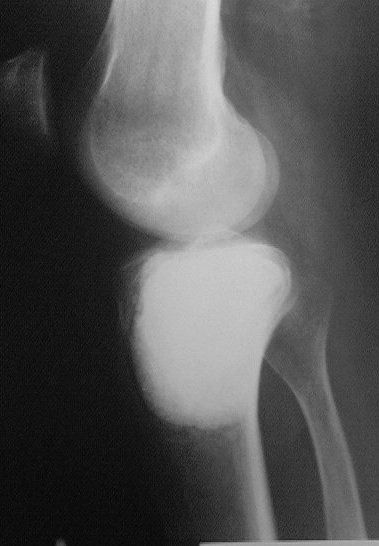

Около года назад больному 25 лет по поводу литической опухоли мыщелка б\б кости ( ОБК?)с выраженным болевым синдромом была произведенарасширенная открытая биопсия, экскохлеация опухоли.

В связи с неясностью диагноза до операции и отсутствия аллокости в тот момент интраоперационно было выполнено экспресс протезирование дефекта мыщелка акриловым цементом. Верхней стенкой дефекта была визуально неповрежденная суставная поверхность. Хрящевая пластина провисала - была выведена на уровень и "подперта" цементным спейсером. Больной осмотрен через год - ходит не хромая, сустав абсолютно спокойный, рентгенологически процедива опухоли нет. Хотелось бы услышать предложения по пластике дефекта - сроки, вид материала. Честно говорябоюсь трогать хрящ повторно.

LP> осмотрен через год - ходит не хромая, сустав абсолютно спокойный,

LP> рентгенологически процедива опухоли нет.

Случай очень интересный! Увидеть бы снимки до операции. Можно обсудить состояние хряща "на цементе"-за счет чего он жив или там все-таки дефект? Щель сустава хорошая. Есть ли возможность проведения МРТ у больного?

Субхондральное эндопротезирование костным цементом при доброкачественных опухолях давно используется в институте им. Вредена. Редко бывают рецидивы (костный цемент, полимеризуясь, нагревается до 70 градусов). Сроки наблюдений благополучного исхода более 20лет.